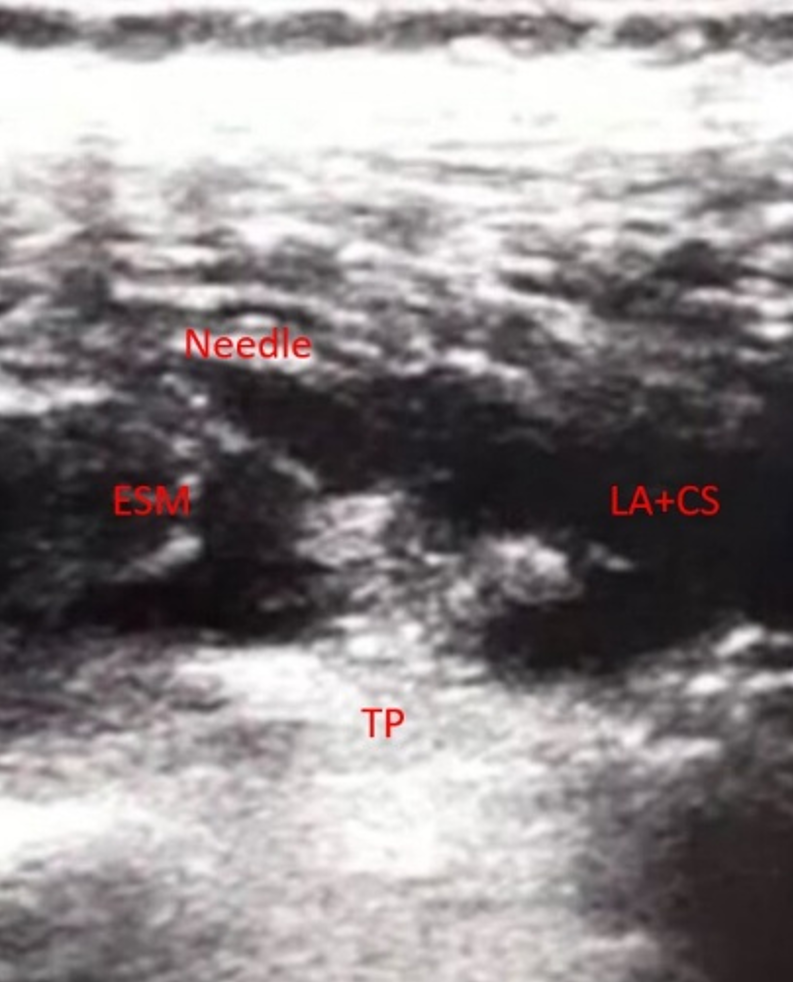

İki yıl önce sivil bir ateşli silah yaralanması sonrası L2 vertebrasında şarapnel parçaları bulunan 28 yaşındaki erkek hasta kronik bel ağrısı ile başvurdu. Hastaya daha önce NSAİİ’ler, gabapentinoidler, antidepresanlar ve opioidler dâhil olmak üzere çeşitli farmakolojik tedaviler uygulanmasına rağmen yeterli ağrı kontrolü sağlanamamıştı. Omurgada yabancı cisim bulunması nedeniyle epidural girişimlerden kaçınıldı. Alternatif bir yöntem olarak T12 seviyesinde ultrason eşliğinde erektör spina plan bloğu (ESPB) uygulandı. İşlem sonrası hastada hızlı ve belirgin ağrı azalması sağlandı; ağrı skorlarında, mobilitede ve yaşam kalitesinde kalıcı iyileşme gözlendi. Bir yıllık takip süresince komplikasyon ya da semptom nüksü izlenmedi ve hasta ek analjezik girişimlere ihtiyaç duymadı. Bu olgu, omurgada retansiyonlu yabancı cisim bulunan ve geleneksel girişimsel yöntemlerin kontrendike olduğu hastalarda ESPB’nin kronik post-travmatik bel ağrısı tedavisinde güvenli ve etkili bir seçenek olabileceğini göstermektedir.